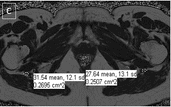

Zoomed images showing the fat fraction measurements. Zoomed image showing the sciatic nerves and their measurements at level A (figure A and B) and level B (figure C and D). (GIF 6 kb)